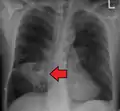

Pulmonary abscess on CT scan

Pulmonary abscess on CXR